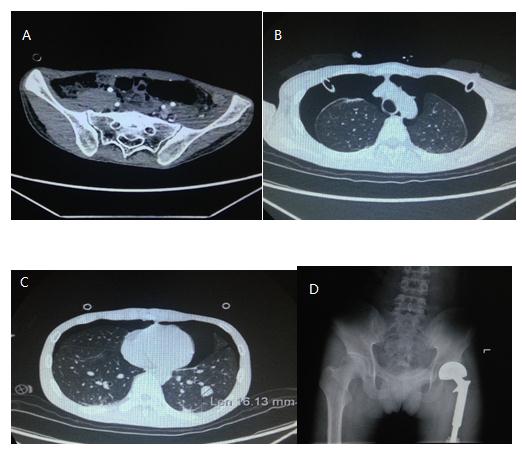

2017-7-17 骨盆CT增强及X线

影像所见:A.左髋人工关节置换术后。左侧髂腰肌及下腹壁软组织肿块影。增强后边缘强化。余骨盆诸骨未见异常。膀胱、前列腺及精囊未见异常。直肠及乙状结肠未见异常。盆腔未见腹水。B.双肺多发结节及肿块影,病灶大小较2017-6-29相仿。双侧气胸引流中,双肺压缩较前加重,双肺压缩约50%。C. 双肺多发大小不等结节及肿块影,最大者位于左肺下叶外基底段,直径约16mm,中央伴钙化。双肺门、纵膈内未见肿大淋巴结。心影及纵膈内大血管未见异常。未见胸腔积液。D. 左髋关节置换术改变。

影像学诊断:左髋人工关节置换术后。左侧髂腰肌及下腹壁软组织肿块,考虑局部复发。双肺转移灶、双侧气胸引流中。